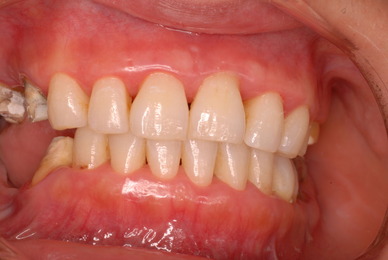

お口の中から差し歯、入れ歯、詰め物を追放しましょう!

口の中の病気を治し、病気を興さない医療を目指します。

二度とお口の中へ変なものを入れなくても済むように

予防に精進いたしましょう!安全な矯正、美容を目指しましょう!